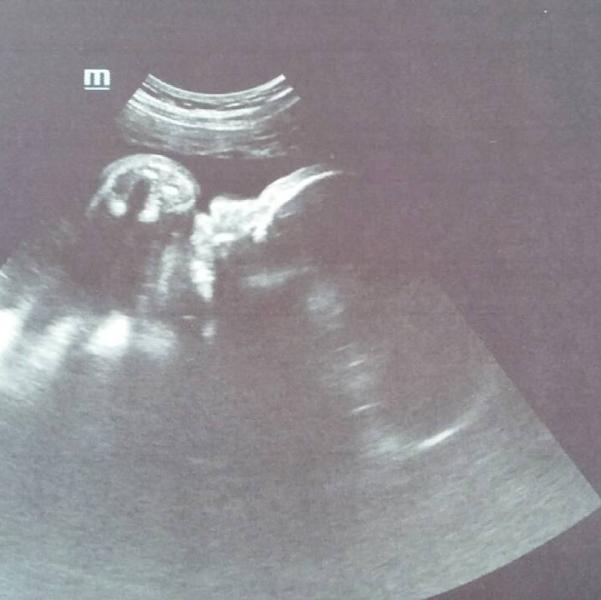

Наш пупс показывает всем кулачек, и говорит- Мамы берегите себя и свою кроху💪😊

Я наконец то за эту неделю, могу спокойно вздохнуть😥С нашим кабачком все в порядке!)😇

Ниже я писала как мы побывали на плановом узи 3 скрининг в 32 недельки.